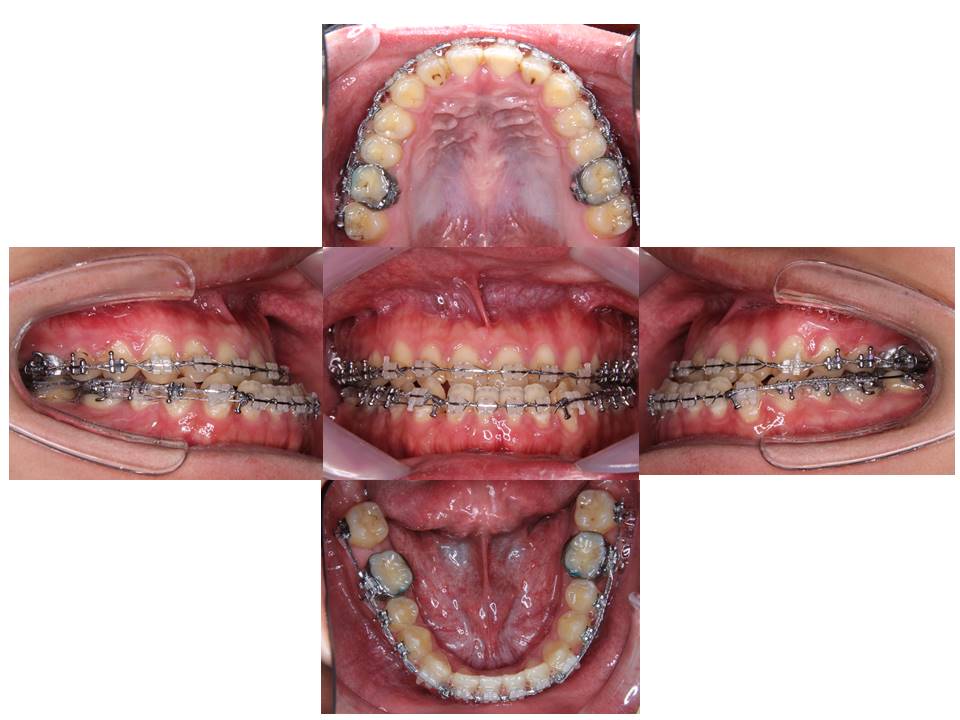

手術直前

下あごの後退を認め、歯と歯の間に存在したスペースはなくなっております。